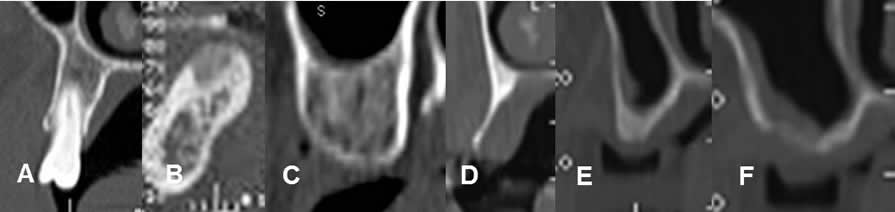

Fig 31. Remodelación del borde alveolar.

TAC reconstrucciones ortogonales.

A: Clase 1. Cresta normal con dientes.

B: Clase 2. Cresta, después de la extracción de una pieza dental.

C: Clase 3. Cresta redondeada, que conservando su altura y espesor.

D: Clase 4. Cresta en filo de navaja, con disminución del espesor, pero conservación de la altura.

E: Clase 5. Cresta plana, con disminución del espesor y la altura.

F: Clase 6. Cresta deprimida, situada entre las raíces de los dientes.